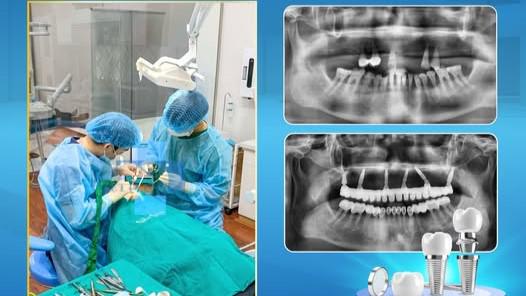

Giải pháp phục hình răng Implant ra đời chính là bước đột phá của nha khoa hiện đại, giúp khôi phục răng đã mất với chức năng và hình dáng gần như răng thật , mang lại sự an tâm và chất lượng sống vượt trội cho người sử dụng.

So với các phương pháp truyền thống như hàm tháo lắp hay cầu răng sứ, Implant sở hữu nhiều ưu điểm vượt trội về cả độ bền, hiệu quả lâu dài và không xâm lấn đến răng thật bên cạnh.

Trồng răng là một trong những giải pháp phục hình hiện đại và hiệu quả nhất hiện nay, giúp thay thế răng đã mất, khôi phục khả năng ăn nhai và đảm bảo thẩm mỹ.